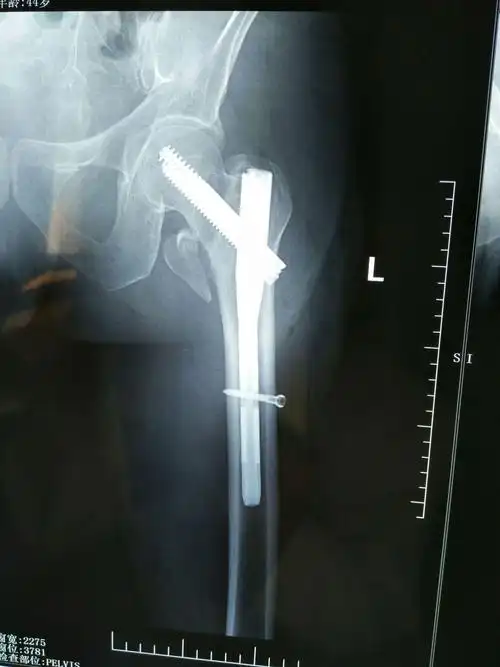

intertan髓内钉内固定病例分享(尧都区人民医院骨三科高峰)

分享一例股骨干骨折,闭合复位髓内钉内固定手术操作流程.

胫腓骨双段骨折闭合复位髓内钉内固定